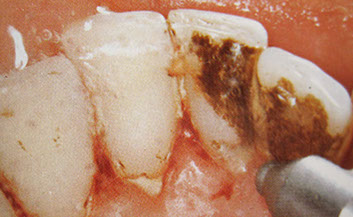

In the first step of cleaning, tartar and plaque are removed from the teeth using ultrasound and Airflow®. The spaces between the teeth are then flossed and cleaned.

Solid deposits, which often form below the gingival margin, are gently removed with special instruments. Gum pockets are also rinsed and disinfected.